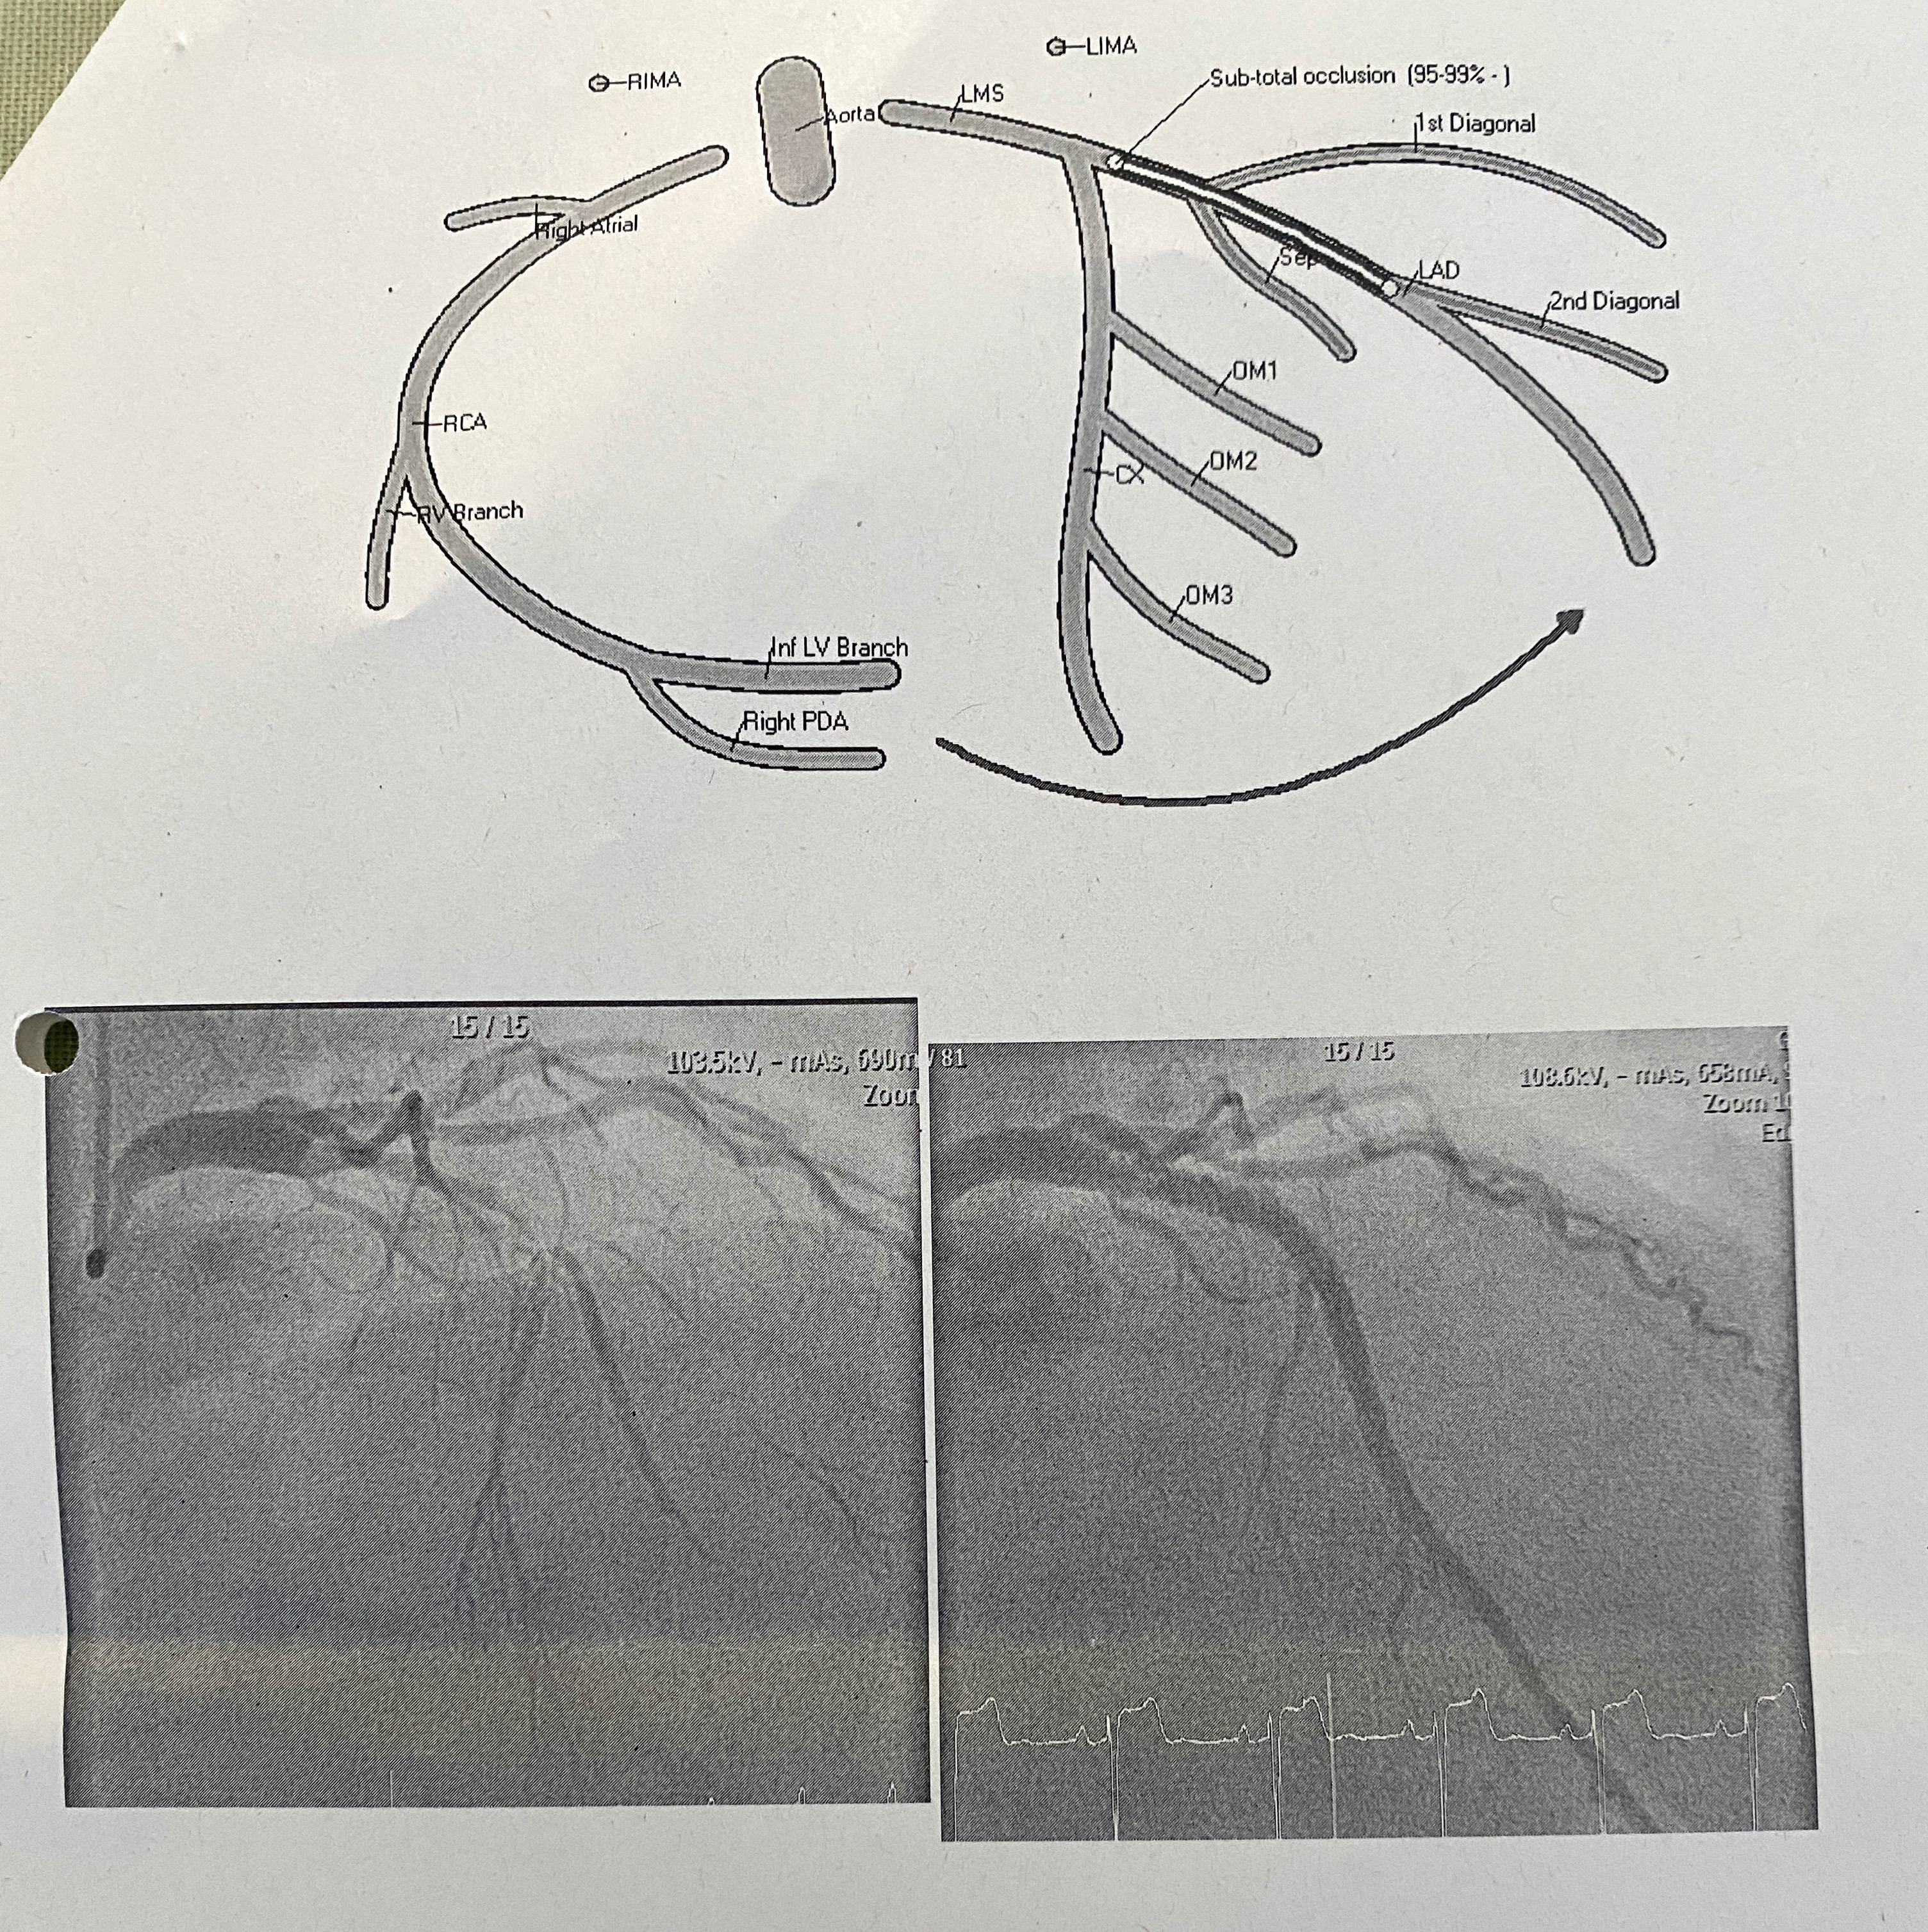

The angiogram went well but they found my Left Anterior Descending (LAD) coronary artery was 95-99% occluded/blocked. They inserted two stents into the artery to open it up and hold it open. All done under a local anaesthetic which is pretty amazing stuff. Three hours later I was out of the theatre with some very painful arms. The left image below is pre-stent with the dye showing the lack of blood flow, the right image is post-stent.